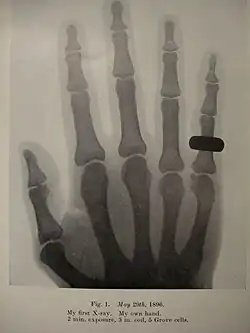

He started research on radiology in 1896, after reading about Wilhelm Röntgen's experiments in this field. Thanks to his meticulous work and advancements in his technique, Holland was able to produce radiographs that were far in advance for many years, compared to the standard practice.[3] Along with such names as Heinrich Albers-Schönberg (Germany), Antoine Béclère (France), Etienne Henrard (Belgium), Guido Holzknecht and Robert Kienböck (Austria), Thurstan Holland is considered one of the pioneers in Europe.[5]